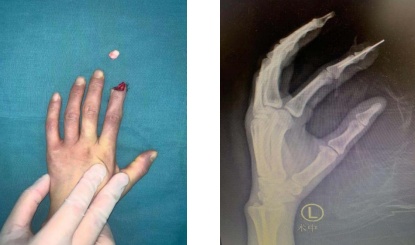

据了解,6月26日下午,胡丽丽在工厂干活时不慎被“油压机”挤伤左示指,致左示指甲根部斜行完全离断,伴疼痛、出血。胡丽丽自幼聋哑,受伤后她立即跑到同事跟前求助。同事见状,立即上报上级,并带着胡丽丽到卫生室简单包扎止血,接着又带她驱车前往betway在线登陆。

到达医院后,急诊开通绿色通道,值班人员通知手外科四病区的医疗团队接诊。专科检查见左示指自甲根部斜行完全离断,创缘不齐,挫伤污染重,创面可见骨折断端外露,活动出血明显,离断指体色苍白。

术前(左图)术中(右图)